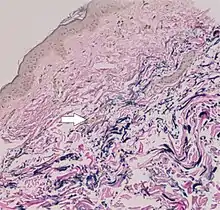

The diagnostic criteria for PXE are the typical skin biopsy appearance and the presence of angioid streaks in the retina. Criteria were established by consensus of clinicians and researchers at the 2010 biennial research meeting of the PXE Research Consortium.[29] and confirmed at the 2014 meeting[30] These consensus criteria state that definitive PXE is characterized by two pathogenic mutations in the ABCC6 or ocular findings – angioid streaks > 1 DD or peau d’orange in an individual <20 years of age together with skin findings:

- Characteristic pseudoxanthomatous papules and plaques on the neck or flexural creases.

- Diagnostic histopathological changes in lesional skin: Calcified elastic fibers in the mid and lower dermis, confirmed by positive calcium stain

| Pseudoxanthoma elasticum | LM: Mid-dermal calcification and fragmentation of elastic fibers EM: Mineralization in elastic fiber core |